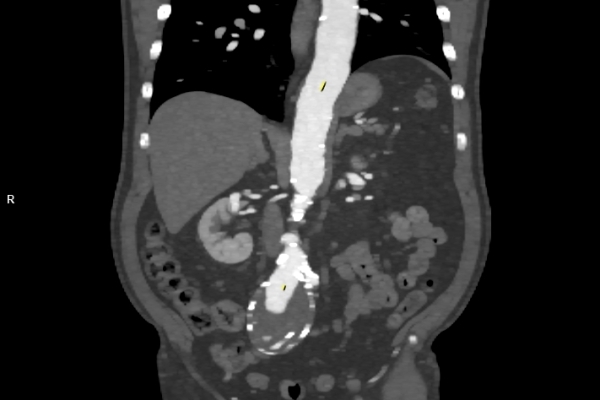

CT Untersuchung Bild

• Gefäßdiagnostik (CT-Angiographie)

Wir bieten ein breites Spektrum an Untersuchungen an, von Standarduntersuchungen der Gelenke, Organe oder großflächigen Körperregionen bis zu Spezialuntersuchungen zum Beispiel des Herzen oder der Gefäße. Zusätzlich werden Angiographien (Darstellung von Blutgefäßen), Endometriose-Abklärungen und Mamma-Untersuchungen durchgeführt. Genauere Details können Sie der MRT/CT-Übersicht und der Preisliste entnehmen, oder Sie wenden sich direkt an unser Team, das Sie gerne zur passenden Untersuchung berät.

Die MRT (Magnetresonanztomographie) arbeitet mit Magnetfeldern und Radiowellen und eignet sich besonders für Untersuchungen der Weichteile wie Gehirn, Muskeln oder Gelenke. Die CT (Computertomographie) nutzt Röntgenstrahlen und liefert schnelle, hochauflösende Bilder, insbesondere für Knochen, Lunge oder innere Organe. Die Wahl der jeweiligen Untersuchung richtet sich an das individuelle Krankheitsbild und wird bei der Überweisung festgelegt.